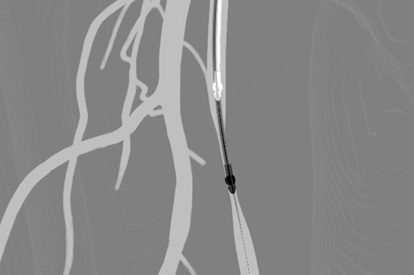

The ANGIO Mentor simulator is an essential tool for clinicians to practice and acquire the skills needed for performing endovascular interventions. Trusted by medical associations, hospitals, training centers, and the medical device industry globally, it provides trainees with realistic clinical settings to practice endovascular interventions using fluoroscopic and ultrasound guidance.

Offers true-to-life simulation of the clinical environment, including advanced imaging modalities like fluoroscopy/echocardiography, hemodynamic monitoring, medications, and interventional devices

Endovascular Basic Skills Module